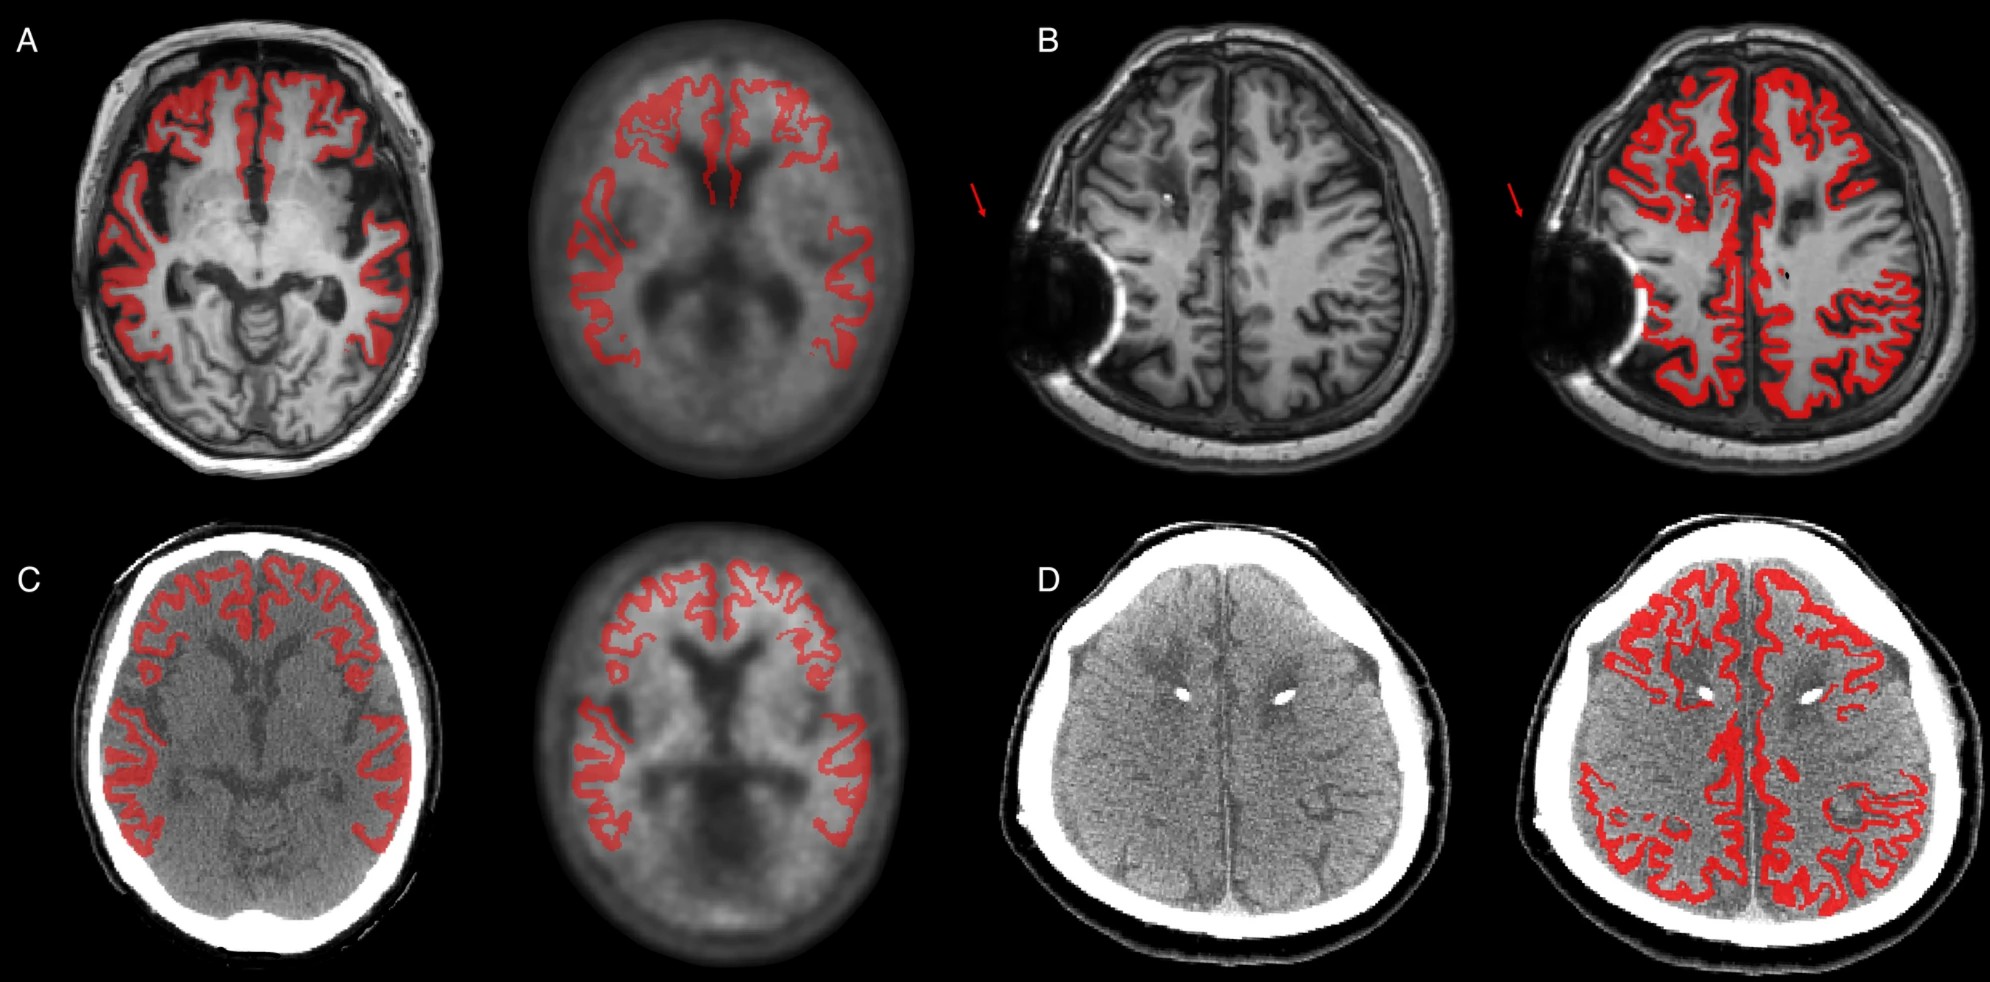

I have developed medical imaging solutions focused on PET and MRI analysis, including dose/time reduction for brain PET and AI-guided prostate lesion detection. I also contributed to automated diagnostic report generation and the regulatory approval of medical software devices (K-FDA).

Hyunkyung Han, Kyobin Choo, Tae Joo Jeon, Sangwon Lee, Seungbeom Seo, Dongwoo Kim, Sun Jung Kim*, Suk Hyun Lee*, Mijin Yun*

Clinical Nuclear Medicine